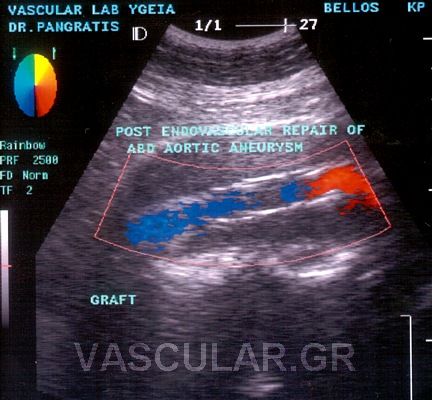

2. Ç åíäáããåéáêÞ áíôéìåôþðéóç êáôÜ ôçí ïðïßá ôïðïèåôåßôáé áðü ôçí ìçñéáßá áñôçñßá åíôüò ôïõ áõëïý ôïõ áíåõñýóìáôïò , åíäáõëéêüò íÜñèçêáò (stent) åðåíäåäõìÝíïò ìå åéäéêü õëéêü ãéá áðïêëåéóìü ôïõ áíåõñýóìáôïò.

Ç ôå÷íéêÞ áõôÞ åéóÞ÷èç êáé Ýãéíå ãéá ðñþôç öïñÜ óôçí ÅëëÜäá óôï íïóïêïìåßï «YÃEIA» áñ÷Ýò ôïõ 1995 áðü ôçí ïìÜäá åíäáããåéáêÞò ÷åéñïõñãéêÞò (Ð.ÌðÜëáò, Í.ÐáãêñÜôçò) êáé åîáêïëïõèåß íá ãßíåôáé ìå Üñéóôá áðïôåëÝóìáôá.

H äéÜñêåéá ôçò åðÝìâáóçò åßíáé 100 +- 30 ëåðôÜ êáé ï ÷ñüíïò ðáñáìïíÞò óôï íïóïêïìåßï åßíáé 3-4 çìÝñåò .

Ç áíôéìåôþðéóç ôïõ áíåõñýóìáôïò êïéëéáêÞò áïñôÞò äé åíäáããåéáêÞò ÷åéñïõñãéêÞò áðïôåëåß ìÝèïäï ãéá åðéëåãìÝíïõò áóèåíåßò , áóèåíåßò õøçëïý êéíäýíïõ êáé ðïõ äåí èá çäýíáíôï íá ÷åéñïõñãçèïýí ìå ôçí êëáóéêÞ ìÝèïäï .

Åí ôïýôïéò ìå ôçí áðïêôçèåßóá äéåèíÞ êáé çìåôÝñá åìðåéñßá ïé åíäåßîåéò åêôÝëåóçò ôçò íÝáò áõôÞò ìåèüäïõ äéåõñýíïíôáé þóôå íá ðåñéëáìâÜíåé áóèåíåßò íåùôÝñáò çëéêßáò êáé óå êáëÞ ãåíéêÞ êáôÜóôáóç.

Ïé ÅíäáããåéáêÝò åðåìâÜóåéò óå áíåýñõóìá ôçò êïéëéáêÞò áïñôÞò (ÁÊÁ) õðåñôåñïýí ôçò êëáóóéêÞò åã÷åéñÞóåùò êáè üóïí ãßíåôáé äé åëá÷ßóôïõ ôñáýìáôïò, ç ðáñáìïíÞ ôïõ áóèåíïýò óôï íïóïêïìåßï åßíáé âñá÷åßá, áðïöåýãïíôáé ïé óåîïõáëéêÝò äéáôáñá÷Ýò óå Üíäñåò êáé ç åðÜíïäïò óôéò êáèçìåñéíÝò åíáó÷ïëßåò åßíáé ôá÷ýôáôç.

Ç éäÝá ôçò áðïêáôÜóôáóçò ôïõ áíåõñýóìáôïò ÷ùñßò áðïêÜëõøç êáé áðïêëåéóìü ôçò áïñôÞò èåùñåßôáé üôé ìðïñåß áêüìç íá ìåéþóåé ôçí íïóçñüôçôá êáé ôçí èíçôüôçôá. Åôóé õðÜñ÷åé óõíå÷Þò åîÝëéîç ìå ôçí ÷ñçóéìïðïéïýìåíç ôå÷íéêÞ áíÜðôõîç êáé äïêéìáóßá íÝùí óõóôçìÜôùí , åê ôùí ïðïßùí ôá ðåñéóóüôåñá åìöáíßæïíôáé áðïôåëåóìáôéêÜ óôïí áðïêëåéóìü ôïõ áíåõñýóìáôïò áðü ôçí êõêëïöïñßá .